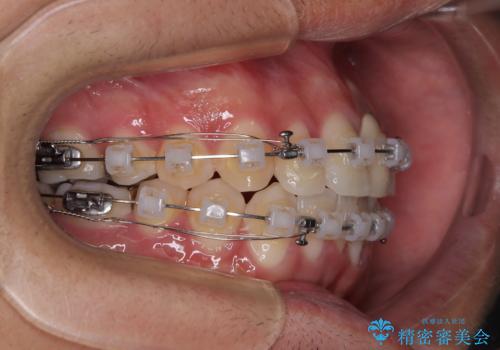

- クリアブラケット

- 治療期間

- 1年10ヶ月

- 治療回数

- 10-30回

上下ともに歯列幅が狭く、その影響でデコボコになっていたため、ワイヤー装置を用いて歯列を側方に拡大しながら、デコボコを解消していくこととしました。